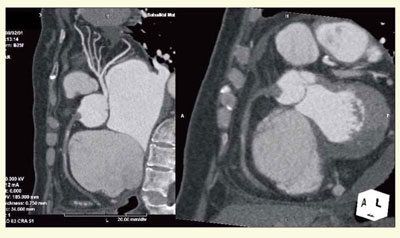

● 症例3:心拍数110,心房細動の評価

急性心筋梗塞で来院した際にカテーテル室が使用中だったため,待ち時間にDSCTを撮影した。心拍数80〜110bpm,心房細動ありの悪条件だったが,βブロッカーを使用せずに画像が得られた(図6)。左冠動脈にプラークはあるが正常で,右冠動脈は入口部から閉塞している。血管造影では冠動脈に異常は見られず,スパズムが関与した心筋梗塞だったことがわかった症例である。

図6 症例3:高心拍・心房細動の急性心筋梗塞例

● 症例4:ステントの内腔評価

CTOに対してPCIを行ったが,最初にガイドワイヤーが新生内膜に入り偽腔を作り,その後に真腔に通し直してステントを留置した。8か月後のフォローアップのCTで,血管内の血流が2つに分かれていることが確認され,OCTを施行したところ二腔構造となっていた(図7)。ステント内腔の評価は,石灰化が少なければ,2.5mm程度でも内膜の確認が可能と考えられる。

図7 症例4:CTOのPCI後の血管内腔評価